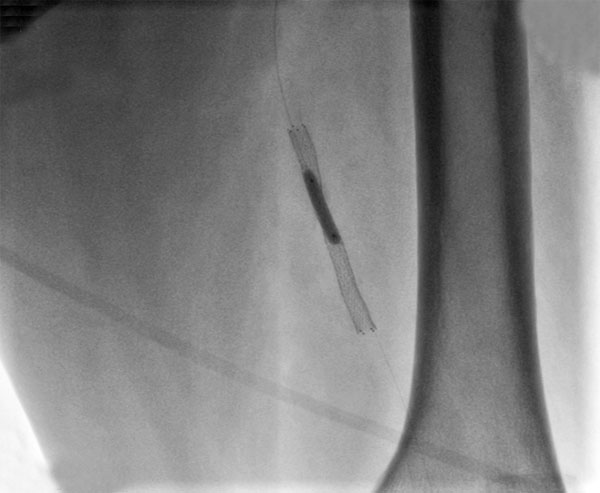

Рис. "Завершение эндоваскулярного этапа - контрольная ангиография: поверхностная бедренная артерия без остаточного стеноза, магистральный кровоток без препятствий, стент раскрыт полностью."